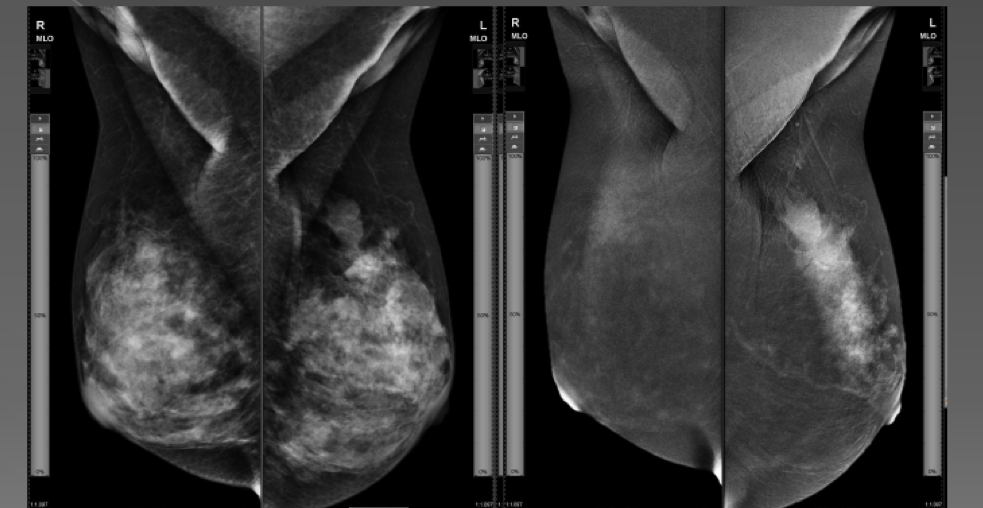

CESM aynı anda iki farklı görünüm oluşturacak spektral ileri veri teknolojisine sahiptir. Normal doku sinyallerinin söndüğü, yoğun süt bezinin örtüldüğü, sadece kontrast madde ile ortaya çıkan tümöral alanların parladığı görüntüler standart mamografi ile tamamiyle aynı pozisyonda elde edilir.

Kan akım patternlerindeki farklılıklar yardımı ile normal meme doku görüntüsünü silen CESM tekniği alışılmış mamogramın 'gizeminden' ayrılarak damardan zengin kanser dokusunun parladığı görüntülere ulaşır.

Endikasyon 3 : Dens – yoğun meme patterni olan olgularda, meme kanserinin tanı ve yaygınlığının değerlendirilmesinde, kontrastlı mammografinin hassasiyet ve doğruluğu digital mammografiye oranla daha yüksektir.